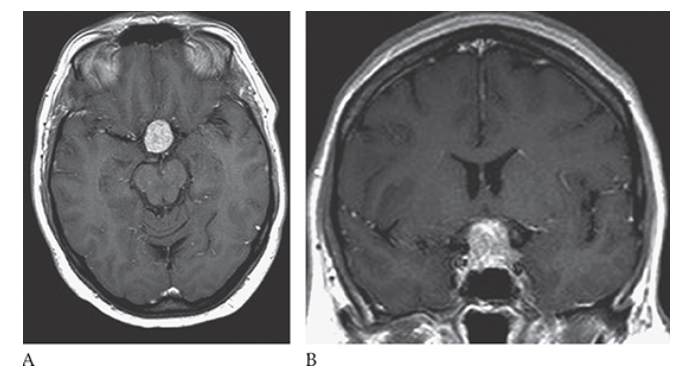

Pituitary Adenoma. Axial T1W MR shows a sellar mass that is isointense to the surrounding gray matter.

What is A

Pituitary Adenoma. Axial and coronal

What is B

Pituitary Adenoma. Axial postcontrast T1W images show heterogeneous enhancement of the mass consistent with a pituitary macroadenoma.